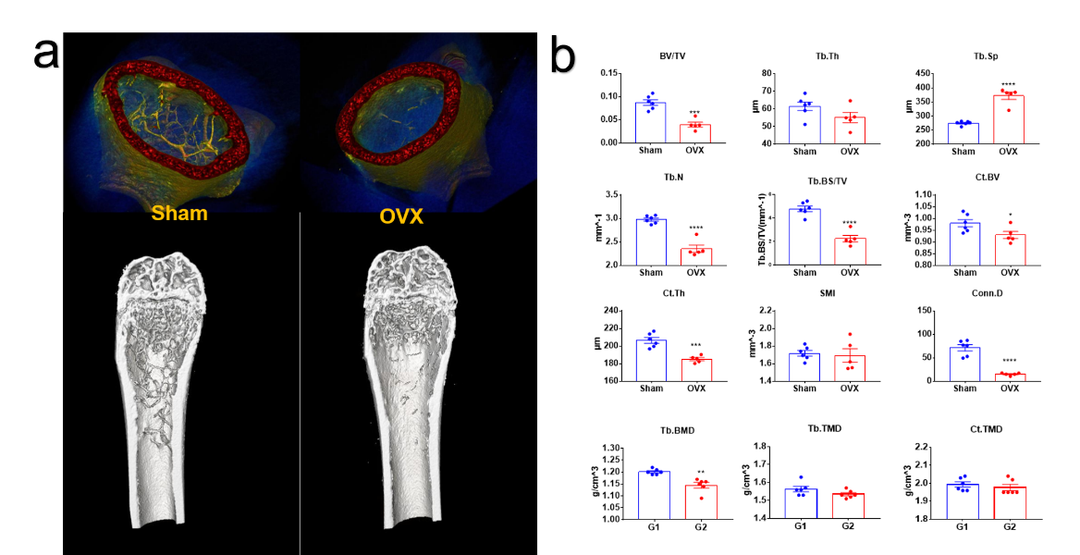

骨质疏松小鼠模型 (Ex/In vivo)-密度属性、结构性参数

卵巢切除诱导的骨质疏松模型离体检测。(a)骨质疏松模型假手术组(sham)和手术组(OVX)3D重建图像。(b)骨小梁、皮质骨结构性参数以及密度属性参数统计图。指标意义参考下方表格,综上结果模型特征明显,手术成功。